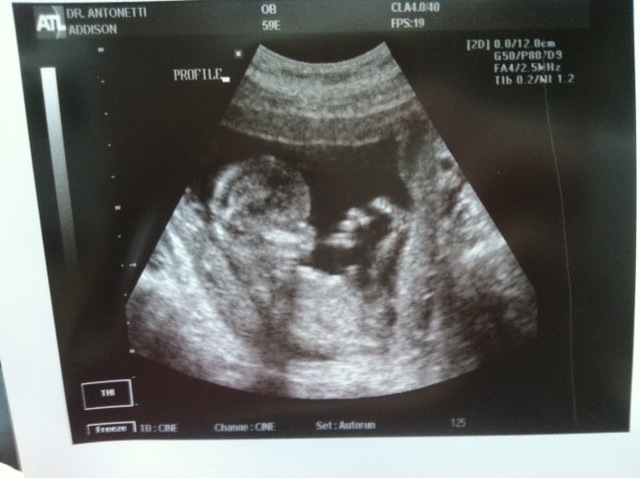

Here it is....But you can't see the nub :-( Baby didn't wanna cooperate lol! Although a few have guessed based on skull theory :-) Attachment 8451